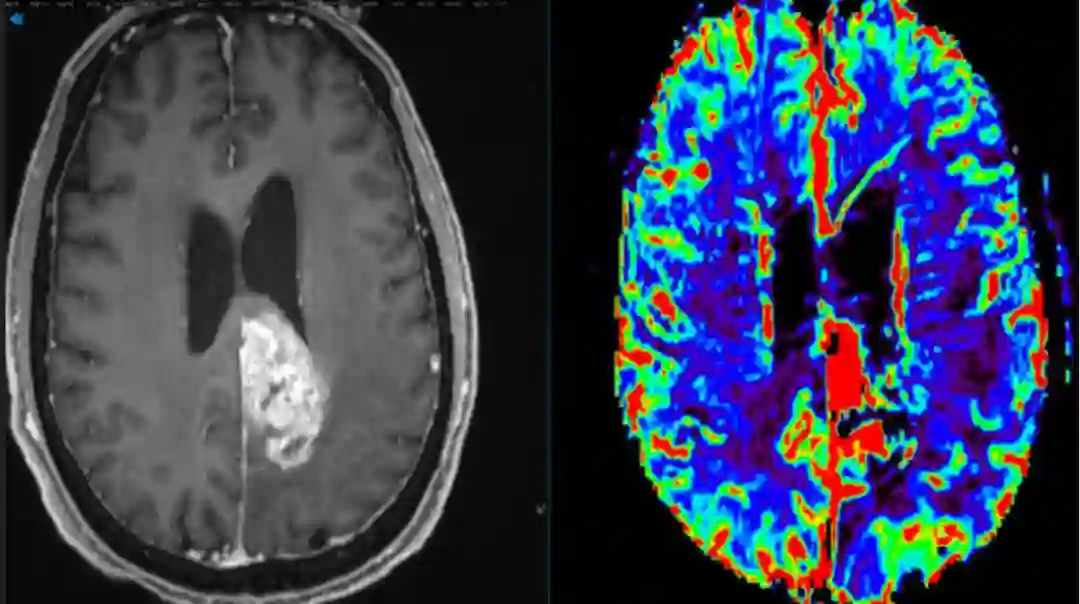

胶质母细胞瘤MRI影像图片。图源:American Brain Tumor Association,abta.org

胶质母细胞瘤(Glioblastoma,GBM),是一种原发性脑部肿瘤,死亡率极高,治愈率偏低,治疗预后差,易复发,是最难治疗的肿瘤之一(图1)

图1. 胶质母细胞瘤。(图源:mayoclinic.org)